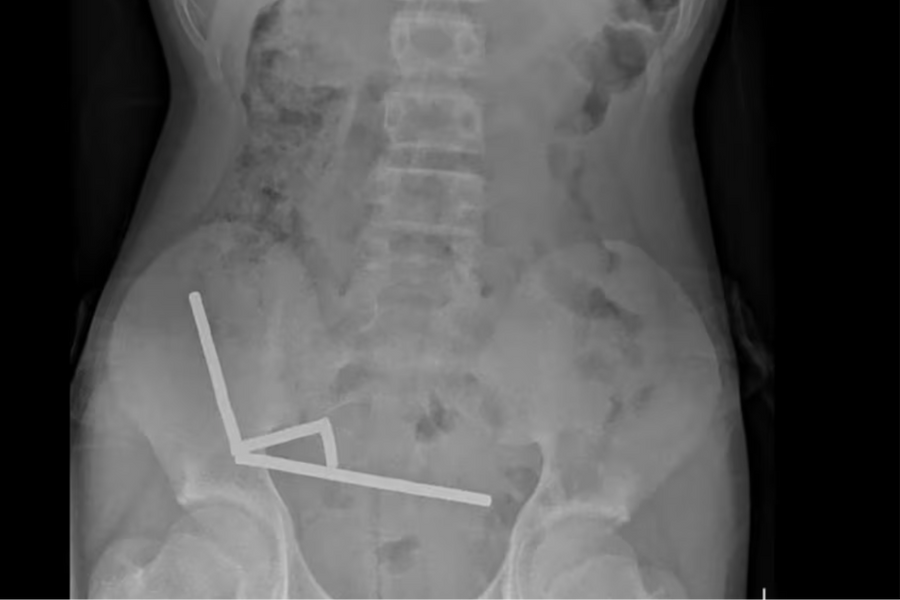

Bé trai phải cắt ruột sau khi nuốt 100 viên nam châm

Một bé trai 13 tuổi ở New Zealand đã phải nhập viện và cắt bỏ một phần ruột sau khi nuốt hàng trăm viên nam châm siêu mạnh.

Bé trai thủng ruột do nuốt hơn 20 viên nam châm xếp hình

Bệnh viện Nhi Đồng thành phố Hồ Chí Minh vừa thông tin về một trường hợp hy hữu xảy ra trên địa bàn.